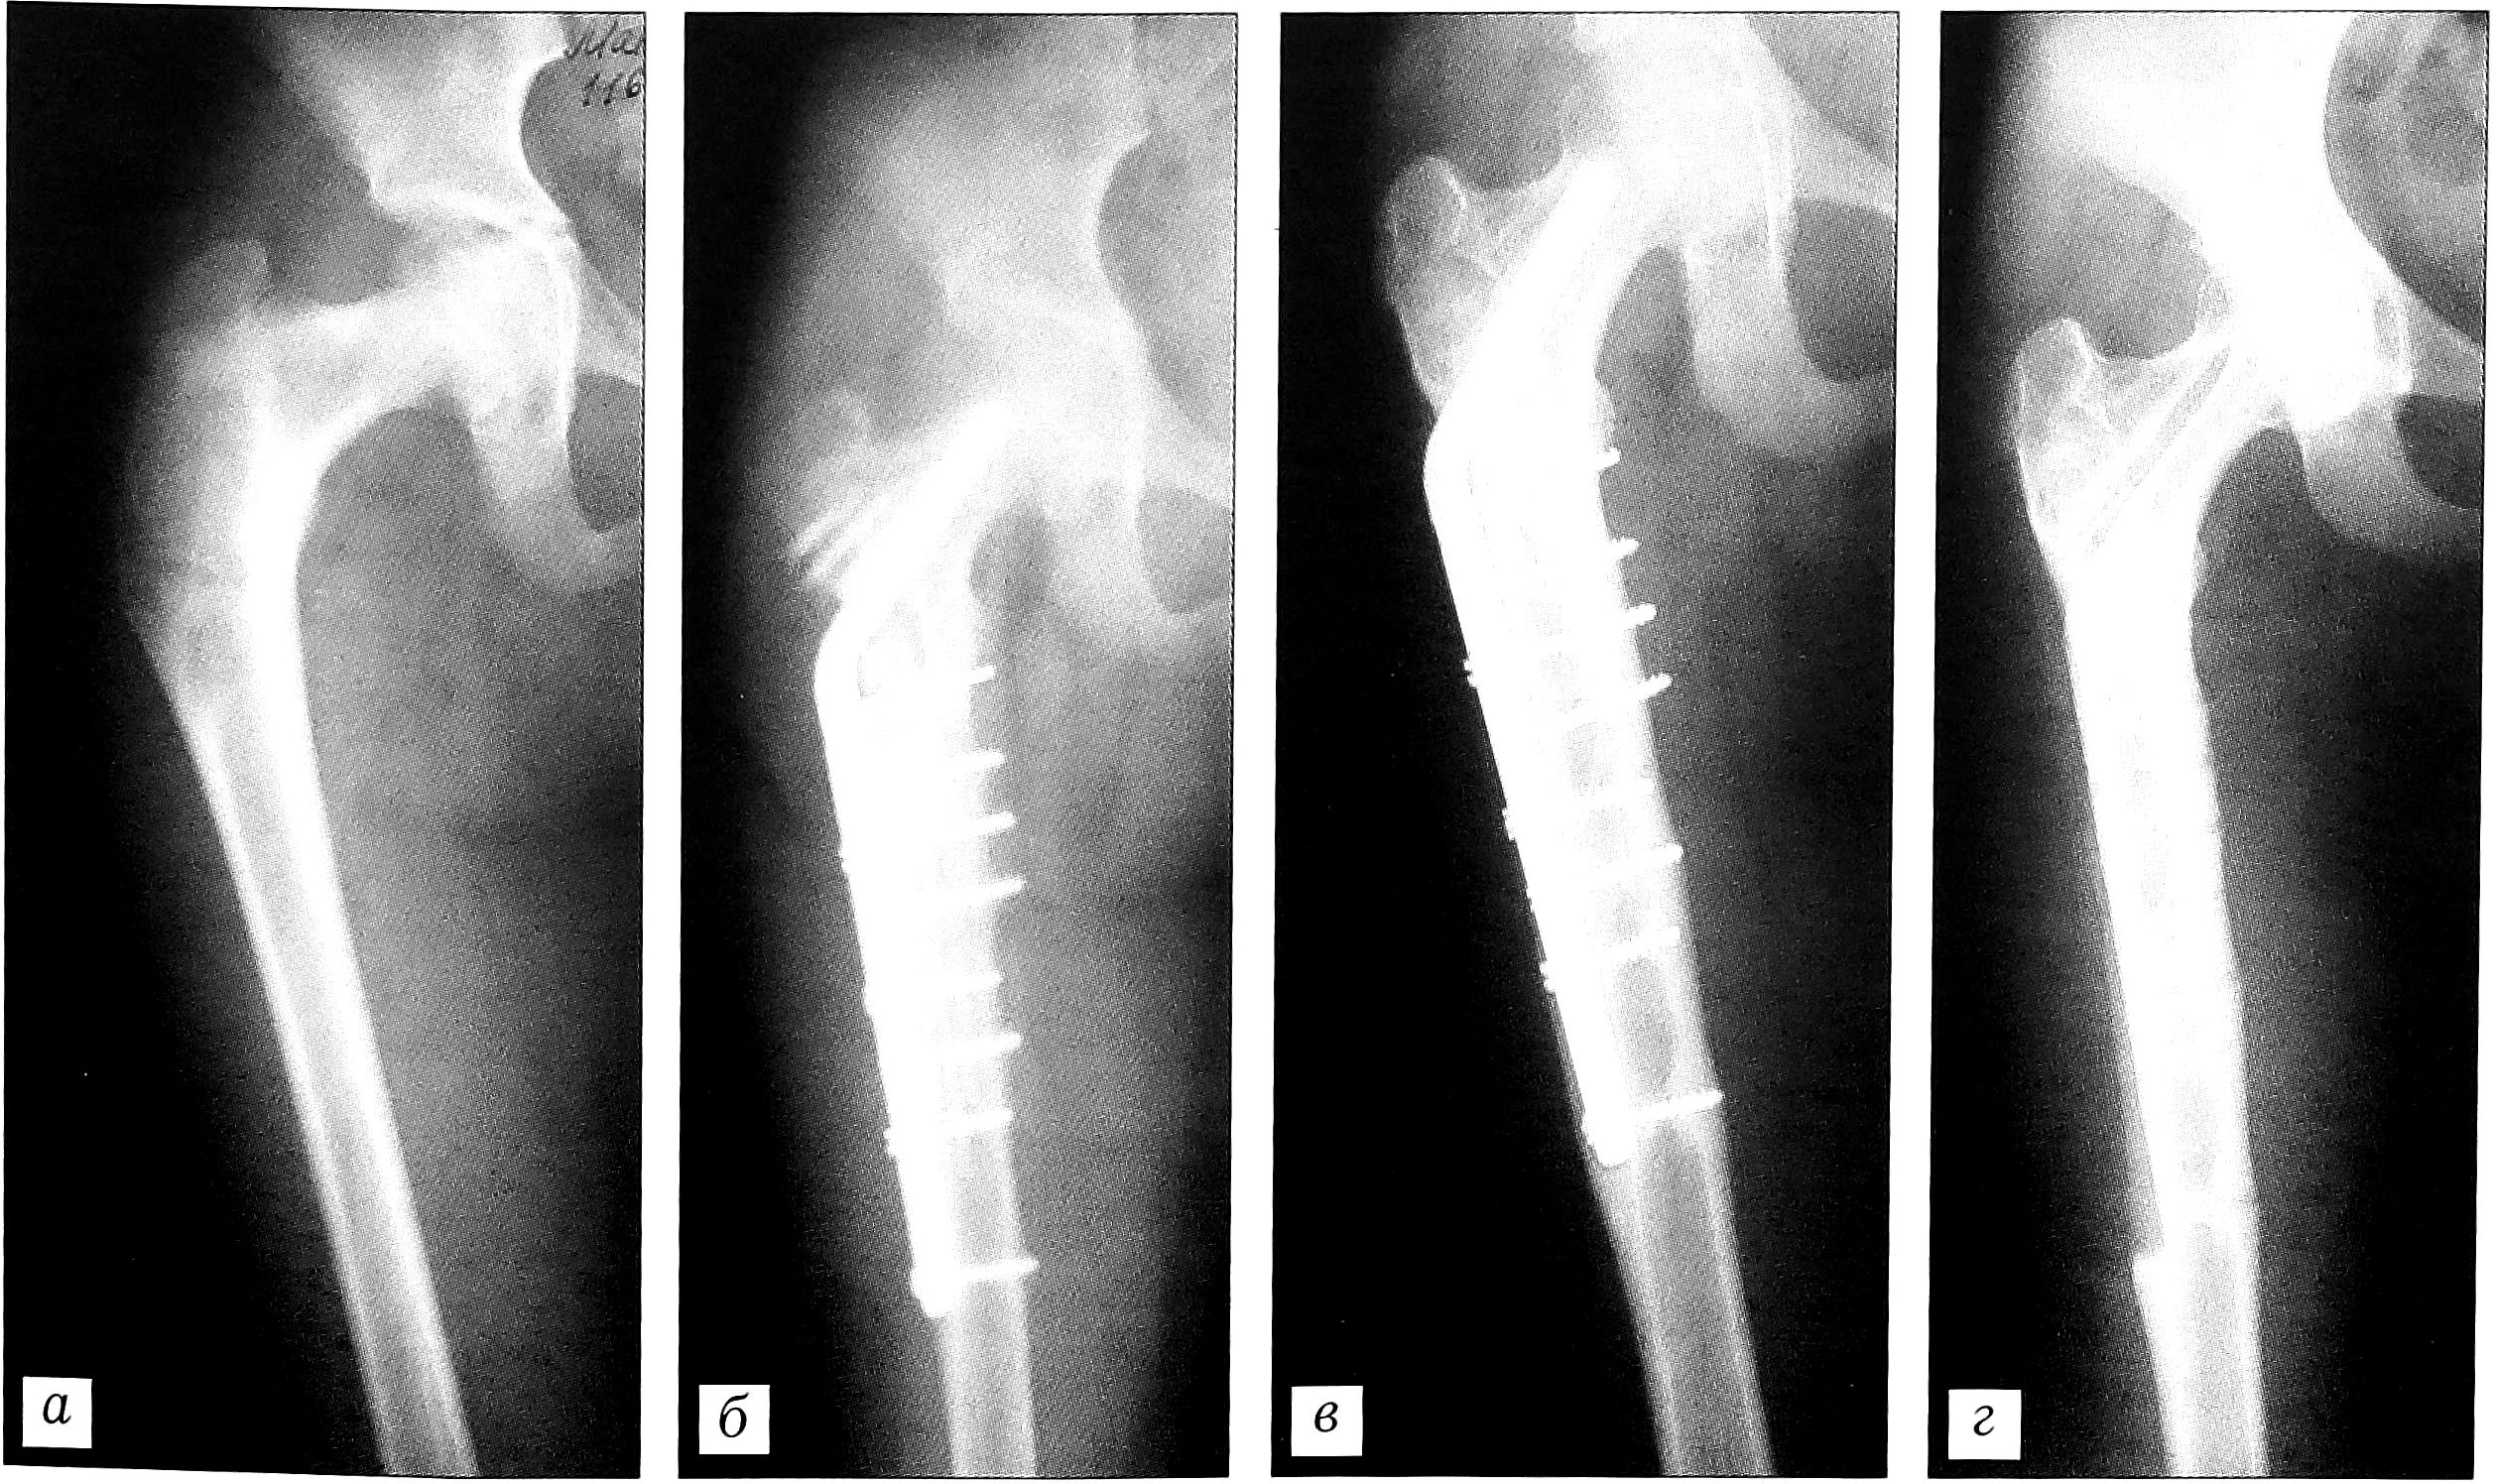

В случае обширных очагов деструкции, занимающих более 1/3 диаметра кости, у больных с очаговой формой фиброзной дисплазии использовали массивные пластины «Перфооста» с наименьшей степенью деминерализации. У 6 больных с диффузным поражением костей при полиоссальной форме фиброзной дисплазии была применена комбинация «Перфооста» с замороженными кортикальными имплантатами, дополненная накостным металлоостеосинтезом. Это создавало условия для радикального удаления патологической ткани с замещением обширного дефекта кости и надежной фиксацией костных фрагментов. Использование поверхностно-деминерализованных имплантатов при таких оперативных вмешательствах способствовало более ранней перестройке пластического материала (рис. 3).

Рис. 3. Рентгенограммы больной М. 16 лет. Диагноз: фиброзная дисплазия правой бедренной кости. а — до операции; б — после обширной краевой резекции и аллопластики «Перфоостом» в сочетании с замороженными кортикальными имплантатами с фиксацией L-образной пластиной; в — через 12 мес; г —через 3 года после операции.